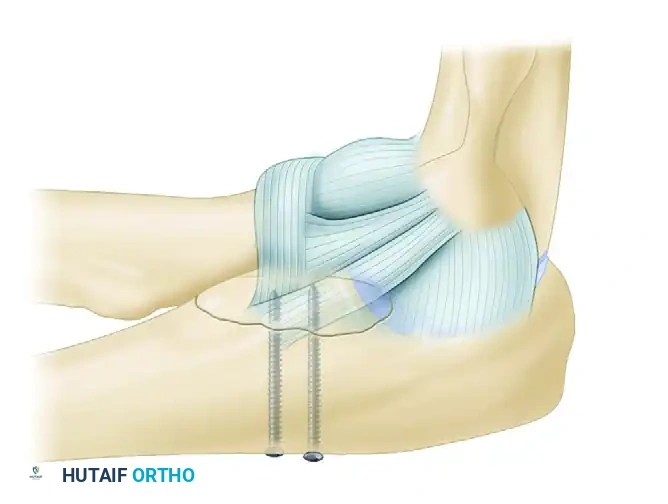

FIGURE 57-67 D: The avulsed lateral ligamentous complex is repaired directly to the bare spot on the lateral condyle using suture anchors.

The isometric point of the LCL is located at the center of capitellar curvature. Reattachment is typically performed using robust suture anchors. Krackow or locking whipstitches are placed into the avulsed ligament and tendon complex, and the anchors are deployed into the lateral epicondyle. Reestablishment of these soft tissue restraints adds greatly to the overall posterolateral rotatory stability of the elbow joint.

If concentric stability cannot be achieved despite adequate bony and ligamentous reconstruction, a hinged dynamic external fixator must be applied. The external fixator maintains joint congruity while allowing the early active motion necessary for cartilage nutrition and prevention of capsular contracture.